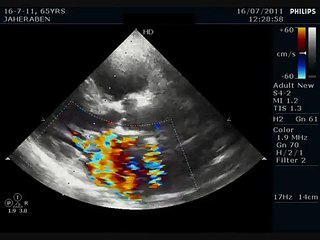

Padezco insuficiencia mitral leve. ¿Cómo puedo darme cuenta si la válvula mitral empeora?

Padezco insuficiencia mitral leve. Me dan taquicardias, mareos y asfixia, pero sólo tomo pastillas para la hipertensión y profilácticos en caso de tratamiento dental. ¿Cómo puedo darme cuenta si la válvula mitral empeora?br br br Consulte a su Médico (Medicable)br br Expertos en el tema nos dan su punto de vista con opiniones personales y gracias a su conocimiento, acerca de enfermedades, cuidados de la salud, información saludable, padecimientos, enfermedades; cualquiera de las preguntas que normalmente nos hacemos.